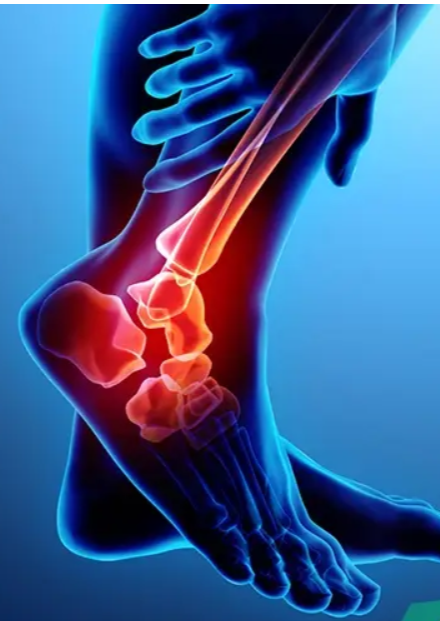

Ankle Sprain

Ankle Fracture

Ankle Syndesmosis Ligament Injury

Ankle Dislocation

Ankle Instability